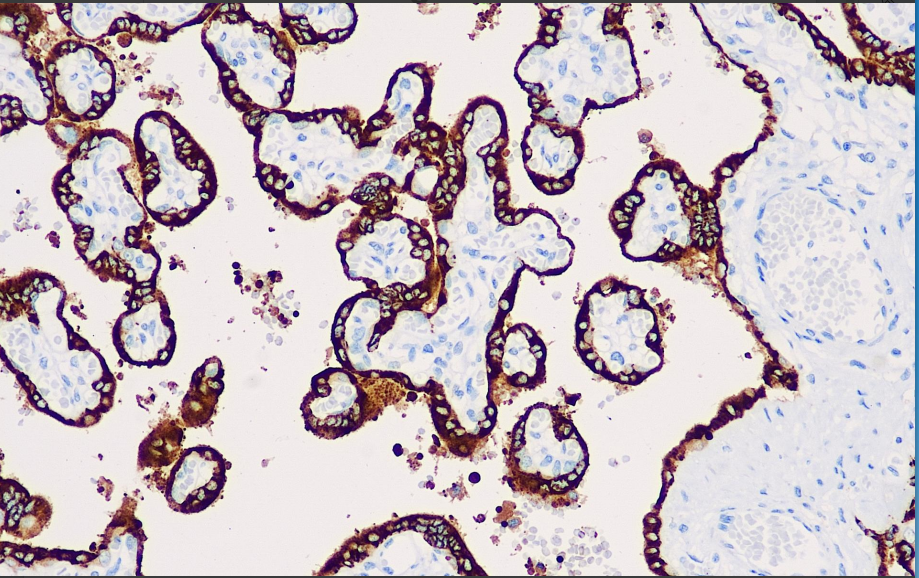

阳性对照: 胎盘

人胎盘催乳素(hPL)被认为起源于合胞体滋养层。超微结构定位表明,胎盘催乳素以小的不同形态的细胞质颗粒存在于这些细胞中,且从不同的激素来源如人类绒毛膜促性腺激素等有不同的分泌机制。妊娠后胎盘催乳素的表达水平会逐渐增加。常见用于绒癌、睾丸癌、乳腺癌和卵巢癌等研究。

hPL抗体试剂可与hPL分子抗原特异性结合,含hPL抗体试剂的免疫组化试剂盒适用于绒癌、睾丸癌、乳腺癌和卵巢癌的精准诊断。